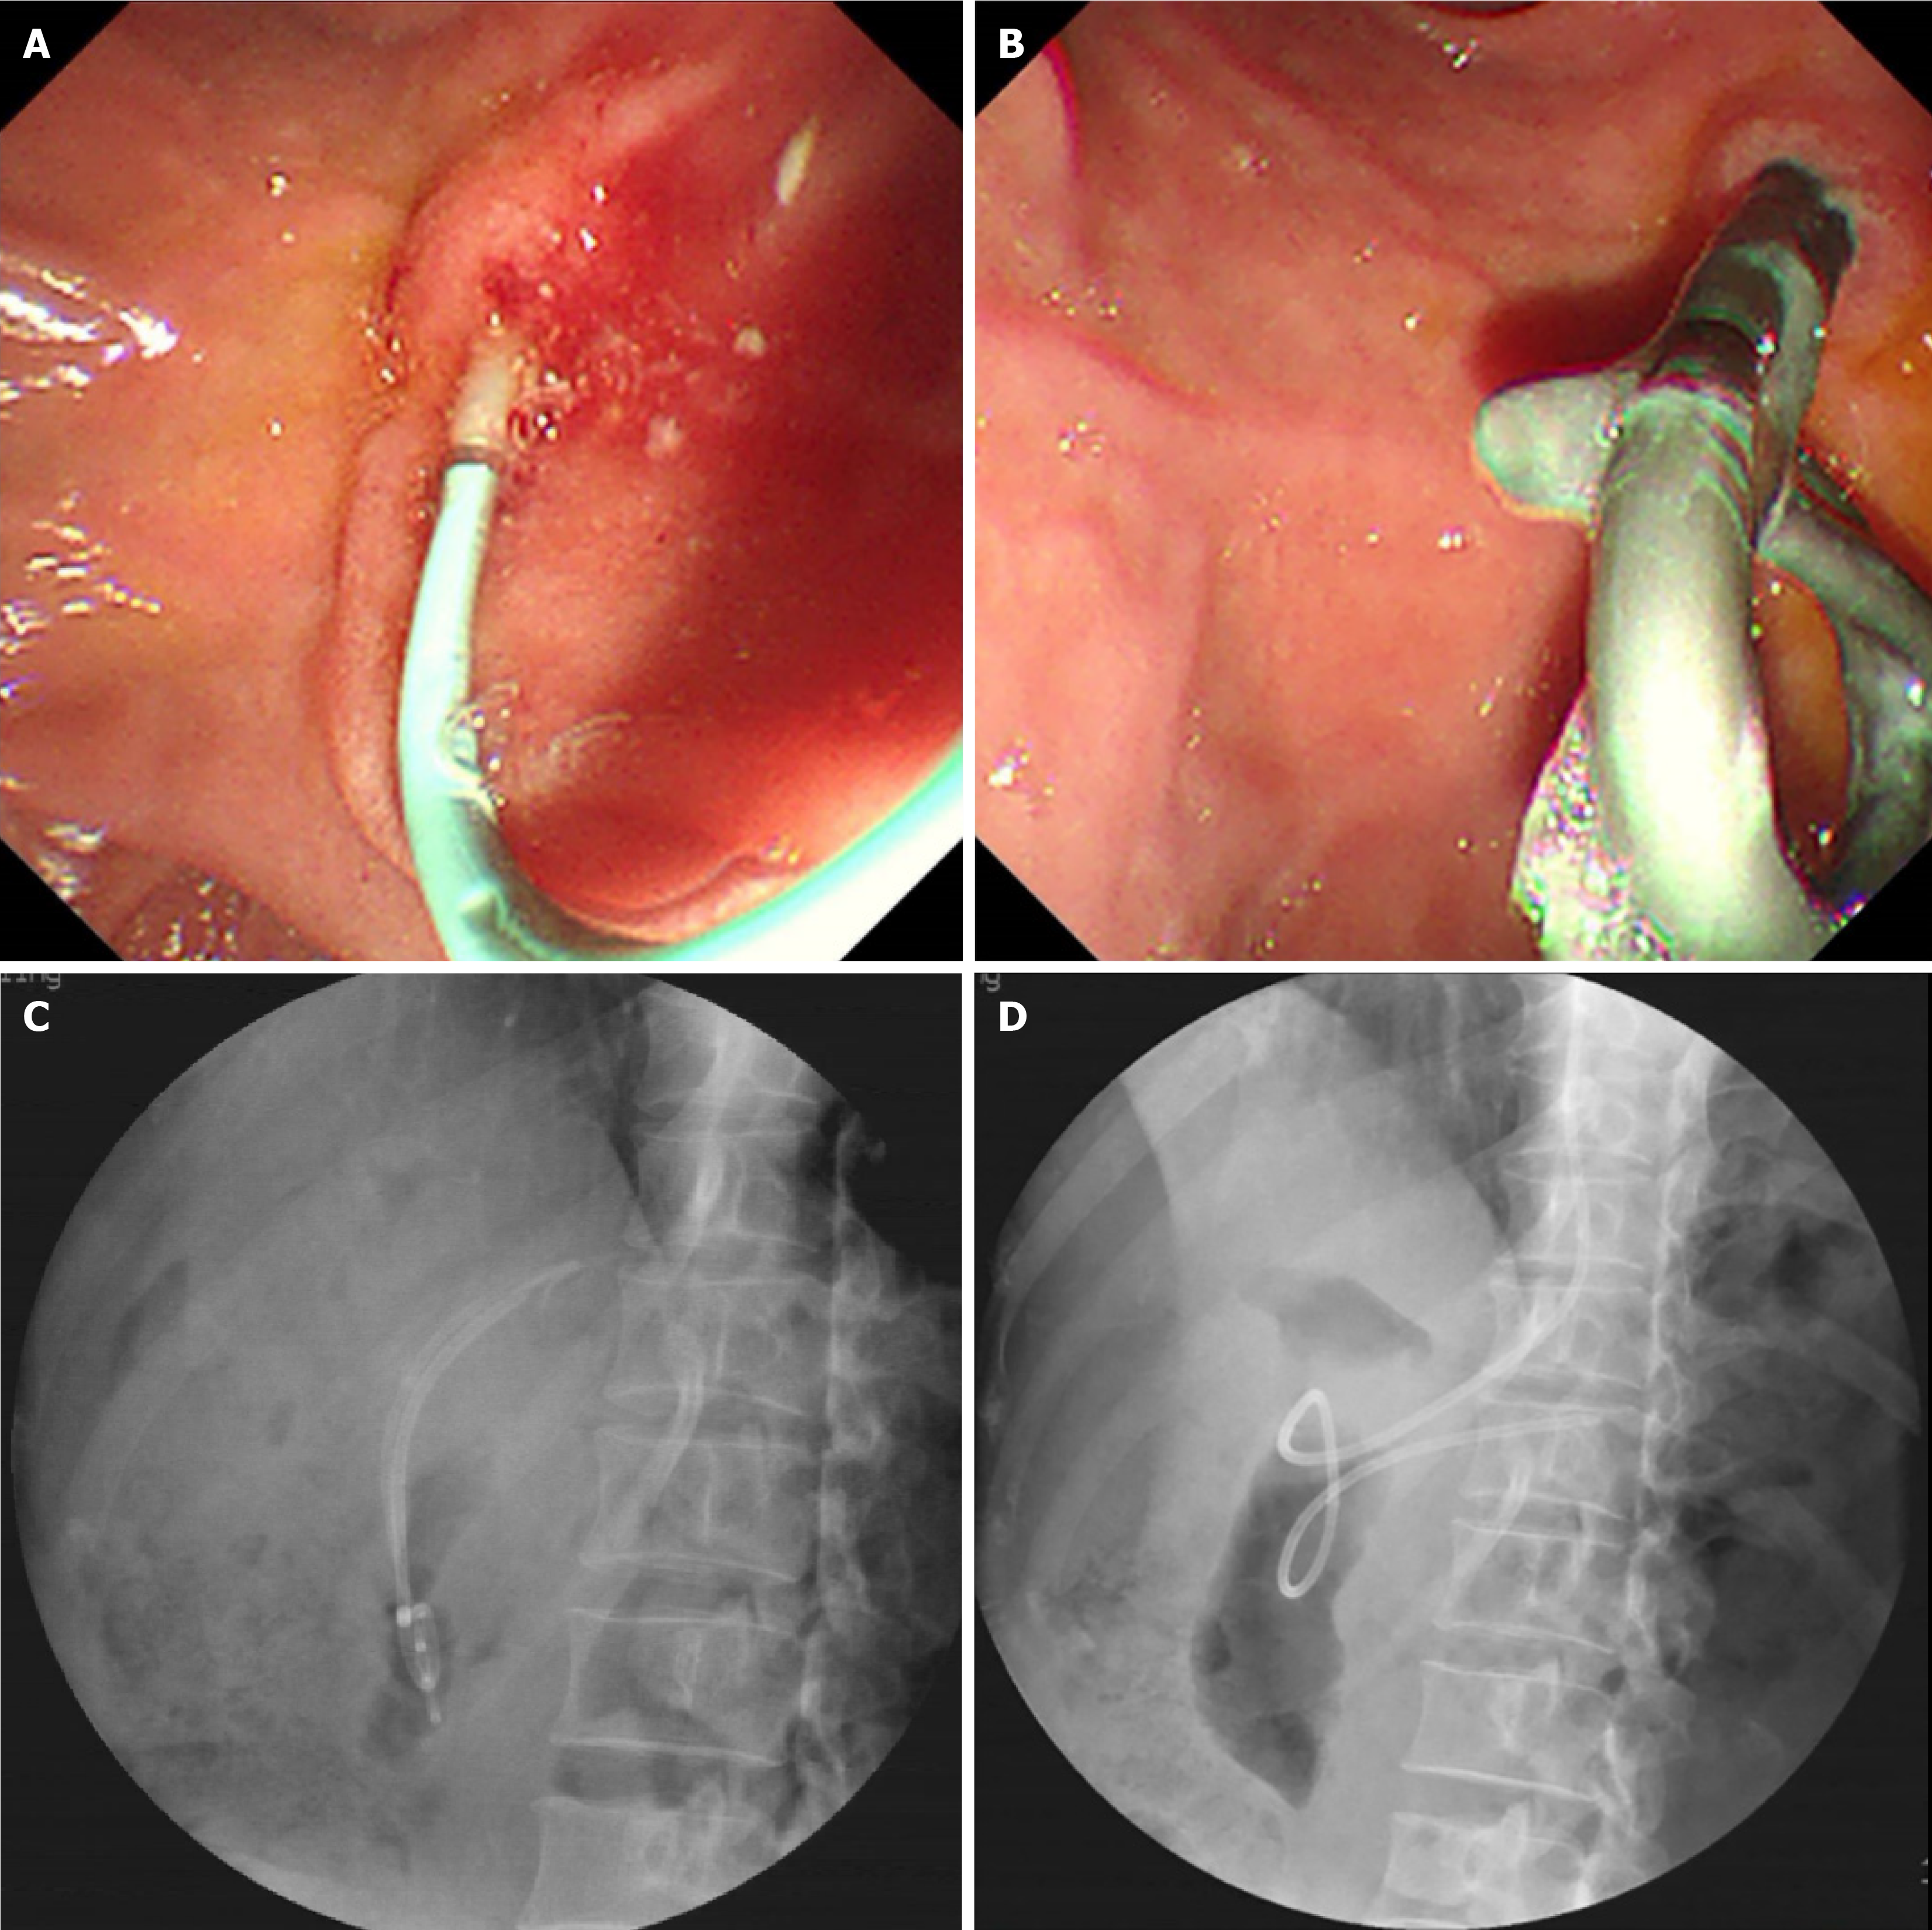

Figure 1 Images obtained during the endoscopic retrograde cholangiopancreatography procedure.

A: The insertion of sphincterotome into the papilla; B-D: Stone extraction balloon cleared the main pancreatic duct, with a straight-shape nasopancreatic stent left in the main pancreatic duct of the pancreatic body-tail.